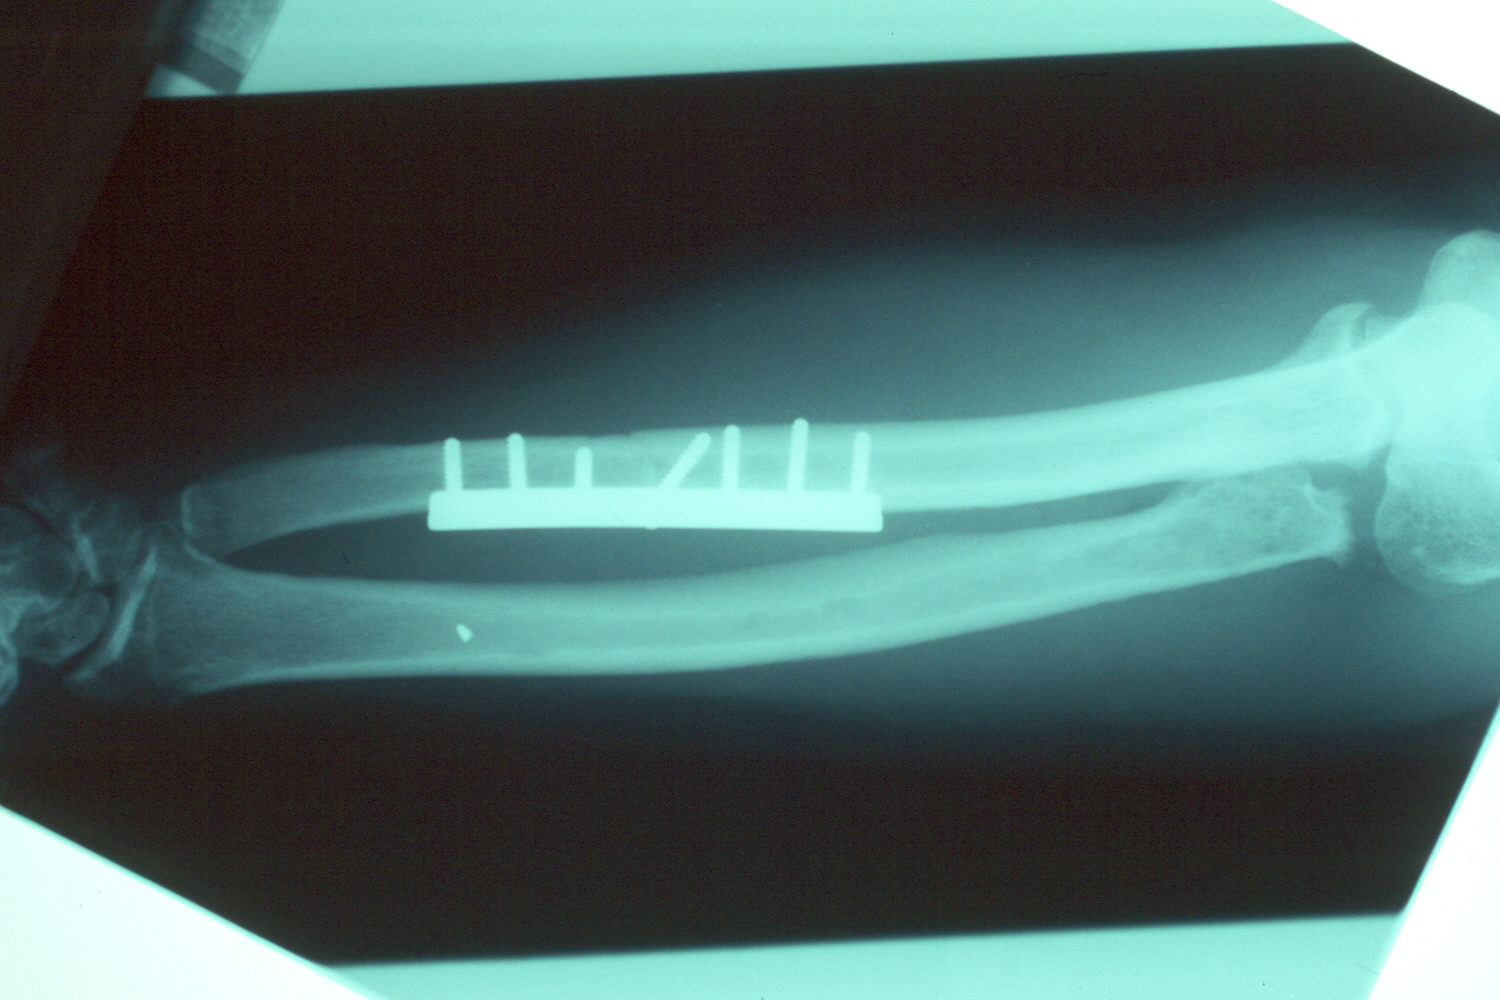

Final appearance of healed osteotomy.

Restoration of normal ulnar length.

Another view of the entire forearm.